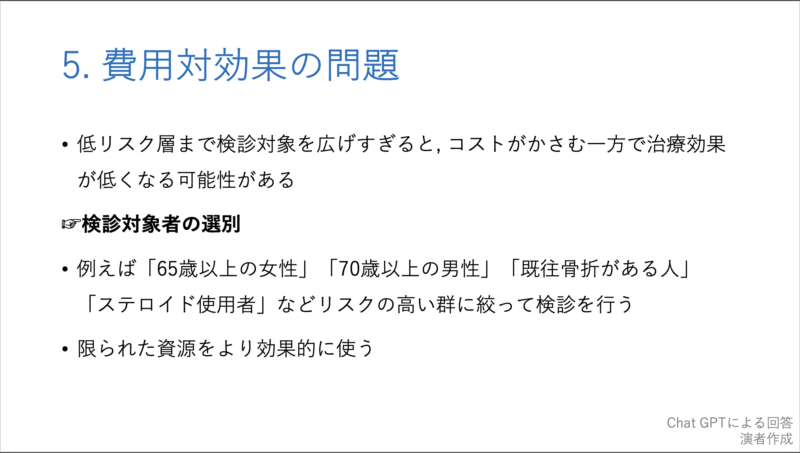

20時過ぎから, 私がclosing remarksとして, 10分で骨粗鬆症検診の問題点とその対策, および各県庁所在地での現状について, チャットGPTからの回答をからめてお話ししました. 途中で, 自分の大腿骨頚部骨折のことも取り上げました.